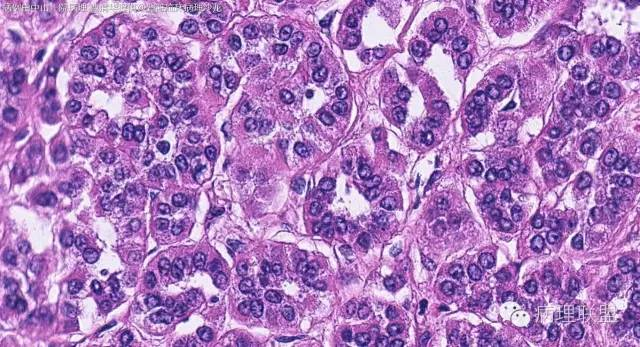

女性,50岁,肾上腺肿物(影像及手术均确认肿物位于肾上腺,界限清楚)。血压升高。(病例由 中山一院病理 曹清华提供,致谢!)

CK,Vimentin,CD56 阳性

inhibina, melana, syn, cga, wt-1, cd57均阴性

从肿瘤的位置及镜下与肾上腺皮质的关系看,应该像是皮质来源肿瘤。假腺样结构的皮质腺瘤没有见过,似乎文献也还没查到。另外inhibina, melanA, syn均阴性(肿瘤旁正常皮质阳)感觉有点迷惑。。。请老师指教,有相关文献么?@武警嘉兴医院 周泉

这个我再仔细看下。但,我们这例腺管结构不像是粘附差所致,是真的腺管;间质目前还没有看到有间质粘液变性区域;inhibina, syn, menlana是真的不阳,灶性都没有...